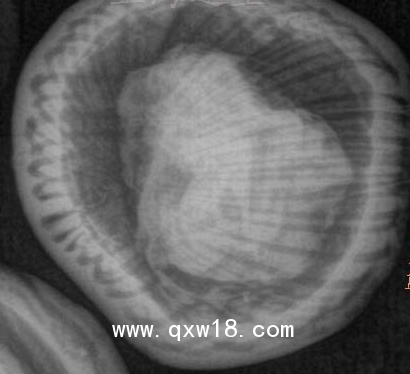

動物X光機

動物、海洋生物檢測儀,采用R160數(shù)字成像系統(tǒng)成像,?0.5微焦點射線管集約束散射線,數(shù)字成像,圖像清晰.儀器全數(shù)字化軟件操作功能;

XDX-DF160B型?動物、海洋生物檢測儀;主要針對動物,海洋生物、魚類檢測;同時還可用于:玩具、蟲草、斷針、金屬異物等檢測